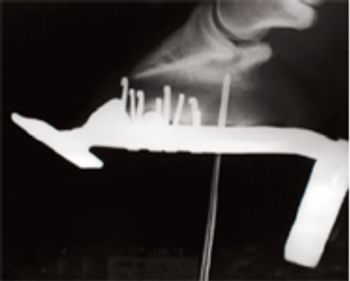

Puncture wounds of the sole in horses can range from simple to complex-even life-threatening-depending on the area of penetration.